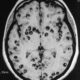

Un joven fue diagnosticado con parásitos cerebrales en México. Conoce cómo la neurocisticercosis amenaza la salud en comunidades con bajo saneamiento. Un caso que refleja una...